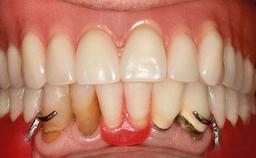

Four Immediately Loaded Mini-Implants Supporting a Mandibular Overdenture

A 74-year-old male patient, a non-smoker, who had been wearing complete dentures for more than 30 years, presented to our clinic complaining about discomfort in connection with his lower denture. The patient suffered from asthma and had a history of cardiac disease and blood pressure disorders. All conditions were medically controlled and stable. The clinical inspection of the oral cavity revealed an ill-fitting complete mandibular denture. The patient expressed the wish for his lower denture to “stop moving when chewing, swallowing, and speaking.” He reported having heard about dental implants and asked whether these could help in “fixing” his lower denture, but also requested non-invasive treatment. The mucosa presented healthy and was free of defects such as pressure sores. An band of keratinized mucosa approximately 2 mm wide was visible. The patient’s mucosal biotype was medium thick to thin.